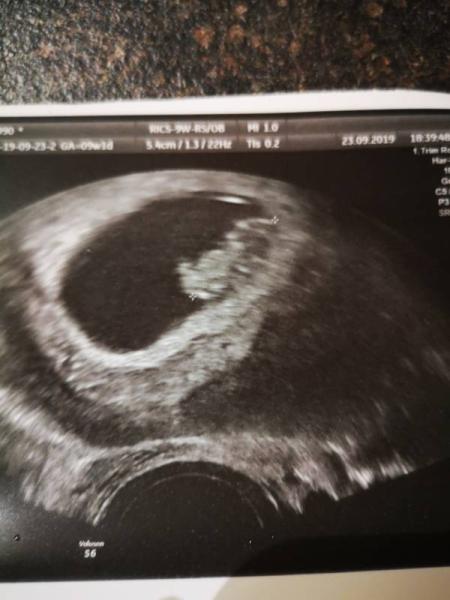

Ich bin soooo happy, der kleine hat sich toll bewegt und alles ist zeitgerecht. Jetzt darf ich wieder arbeiten gehen. Hoffe allen gehts gut hier.

Bild zu Heute FA Termin bei 9+1 - Forum für April - Mamis

Ich hatte bei 8+1 hellrote Blutung, im Ultraschallbild sah mann das unter Fruchthöhle sich einstück gelöst hat. Das Problem war nur das gleiche hatte ich im Frühjahr auch schon und da endete es in einer Fehlgeburt. Das schöne ist das dieses Kind ein Lotto 6 ist da wir eigentlich in einer Kinderwunschklinik Patienten sind (versuchen es seit 6 Jahren). Das Kind was ich im Frühjahr verloren habe war durch eine Kryotranfer entstanden, dieses ist lustiger weiße auf normalen Weg entstanden (jeder arzt hat uns gesagt das kann bei uns nicht auf normalen Weg klappen) und siehe da. Ein keines Wunder.